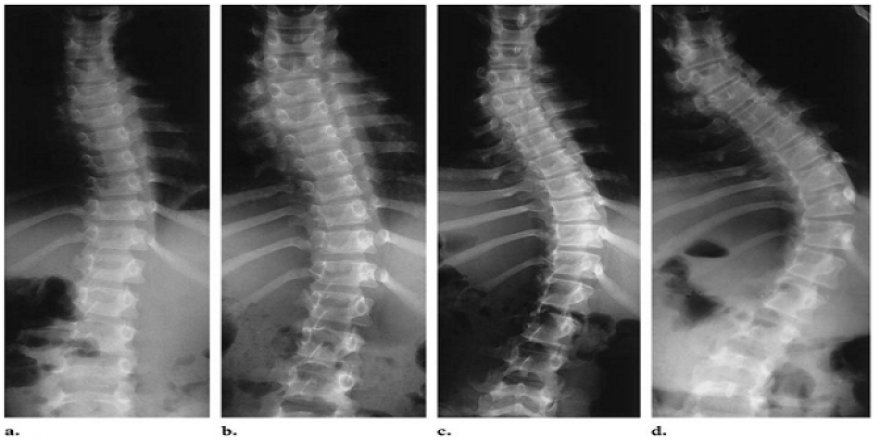

Fındıkzade Medipol Üniversitesi Hastanesi Fiziksel Tıp ve Rehabilitasyon Uzmanı Dr. Şadiye Sarataş, skolyoz açısından özellikle kız çocuklarının risk altında olduğunu belirterek önemli açıklamalarda bulundu. Dr. Sarataş, omurganın sağa veya sola doğru 10 derece üzerindeki eğriliğine skolyoz denildiğine dikkati çekerek, "Skolyoz sadece tek boyutlu bir açısal deformasyon olmayıp omurga aynı zamanda kendi eksenleri etrafında döner yani vücudu üç boyutta etkileyen bir kemiksel ve yapısal bozulmadır. Skolyozun belirtileri, omuzlardan birinin diğerine göre yüksek olması, kalçanın sağa/sola doğru kayması veya bir tarafta kalçanın yüksek durması, kürek kemiklerinin duruşunda eşitsizlik, bacaklara göre gövdenin orantısız kısalığı, denge bozukluklarıdır. Skolyoz, erken dönemde hiçbir sağlık problemi oluşturmaz, nadiren sırt ve bel ağrısı görülebilir." dedi.

Dr. Sarataş, skolyozun daha çok kız çocuklarında görüldüğüne dikkati çekerek şu bilgileri verdi: "Skolyoz ile ilgili bilimsel araştırmalar genetik geçişi sorumlu tutmaktadır. Skolyozlu bireylerin birinci derece akrabalarının yüzde 30'unda, ikinci derece akrabalarının ise yüzde 12.5'inde skolyoz olduğu ve bazı ırklarda bunun daha belirgin olduğu gösterilmiştir. Kız çocuklarında skolyoz daha çok görülür ve ilerleme daha fazladır. 10 derecenin altındaki eğriliklerde kız ve erkeklerde görülme oranı eşit iken, 30 derecenin üstündeki eğrilikler kızlarda 10 kat daha fazla görülmektedir. Henüz bilinmeyen nedenlerle kızlarda erkeklere göre ilerleme de 10 kat fazladır. Profesyonel rekabetçi yüzme ve klasik bale eğitimi ile ilgilenen ergenlerde skolyoz riskinin arttığını gösteren çalışmalar mevcuttur. Öte yandan, skolyozun eğrilik açısı arttıkça, akciğerlerin ve kalbin göğüs kafesinde sıkışması nedeniyle, nefes darlığı, şişkinlik, çabuk yorulma gibi şikayetler ortaya çıkabilmektedir. Skolyoz hastalarının uzun süreli takip çalışmalarında ölüm oranı genel popülasyonla aynıdır. Akciğer ve sağ kalp yetmezliğinden artan ölüm oranı sadece ciddi sırt eğrilikleri olan (90 derecenin üzerinde) hastalarda görülür."